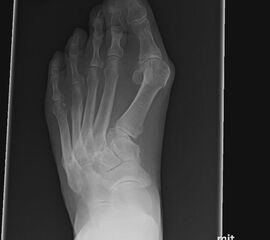

Bei nicht traumatischen Arthrosen am Tarsometatarsale (TMT) II und III Gelenk handelt es sich meist um proximale Überlastungsschäden bei ausgeprägtem Spreizfuß mit Instabilität im TMT I Gelenk oder auch alleiniger Hypermobilität im TMT I und dadurch fehlender Lastaufnahme über den ersten Strahl.

Häufig werden die Arthrosen der Lisfranc-Gelenklinie relativ spät diagnostiziert. Die Gründe dafür liegen oft daran, dass die Patienten selbst einen Schmerz an der Fußwurzel nicht mit dem Symptomkomplex Spreizfuß und Hallux valgus in Verbindung bringen. Auch werden in der Primärdiagnostik häufig nur vom Vorfuß Röntgenbilder angefertigt oder die angewandte Röntgentechnik erlaubt keine Einsicht in die Lisfranc-Gelenklinie.

Der ausgeprägte Spreizfuß führt bei vielen Patienten zu einer verringerten Lastübernahme am ersten Strahl. Ursache sind das medialisierte Os metatarsale I, sowie eine Hypermobilität im TMT I Gelenk. Unter Belastung weicht das Metarasale I nicht nur nach medial sondern auch nach dorsal aus, was die Belastung der Ossa metatarsalia II und III erhöht. Das typische klinische Symptom ist eine Transfer­metatarsalgie. Diese kann bereits bei einer isolierten Hypermobilität im TMT I auftreten. Sobald es zu einer isolierten Elevation des ersten Strahles unter Belastung kommt, steigt die Beanspruchung der medialen Metatarsalia. Weniger häufig sind posttraumatische Arthrosen, die nach Frakturen an den Basen der Metatarsalia oder (Sub-) Luxationen in der Lisfranc-Gelenklinie entstehen.

Es gibt neben der Möglichkeit mit der in situ TMT II, III Arthrodese auch die Möglichkeit Fehlstellungen wie den Pes metatarsus adductus zu adressieren (Abb. 9 und Abb. 24 zeigen das prä- und postoperative Röntgenbild eines Patienten mit Pes adductus Korrektur).